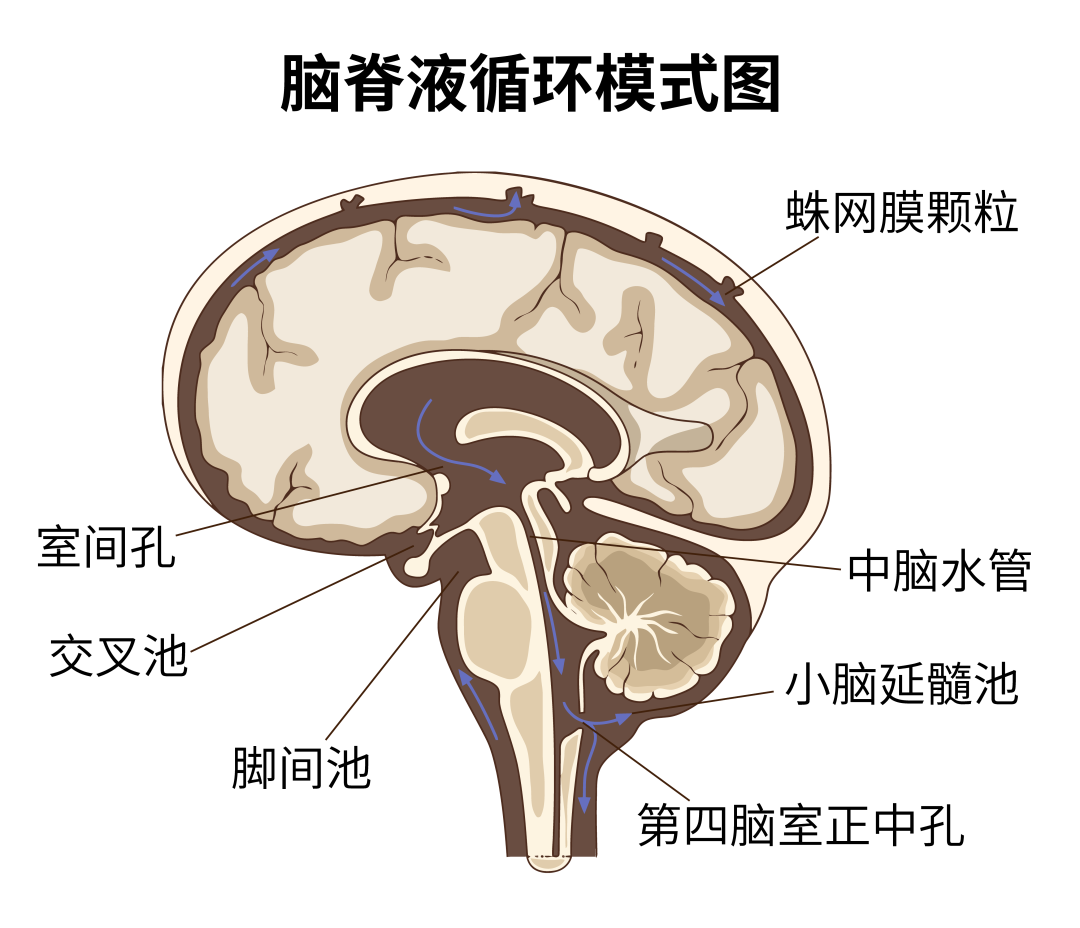

脑子里的“水”在医学上叫脑脊液,是无色的透明液体,人体每天都会产生一定量的脑脊液,其作用是为脑细胞提供营养,并运走脑组织的代谢产物,起到缓冲大脑和脊髓压力的作用。一般情况下,脑脊液是在颅内产生和循环,与外界不相通。

图源:深圳卫健委